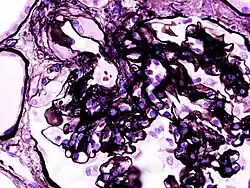

_PAM.jpg)

Secondary causes of nephrotic syndrome have the same histologic patterns as the primary causes, though they may exhibit some differences suggesting a secondary cause, such as inclusion bodies.[24] They are usually described by the underlying cause, such as: